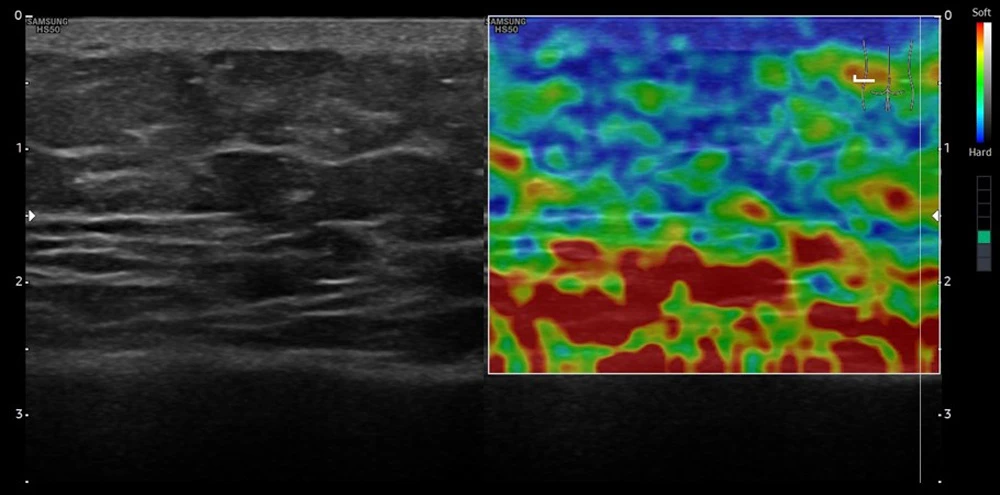

Эластосканы пациента после окончания лечения. Правая сторона

После курса лечения у пациента в тех же исследуемых участках при поверхностном сканировании в тех же точках наблюдалась значительно более высокая жесткость ткани (на снимках окрашены в синий и зеленый цвета).

Отмечается увеличение прочности на границе кожи и подкожной клетчатки.